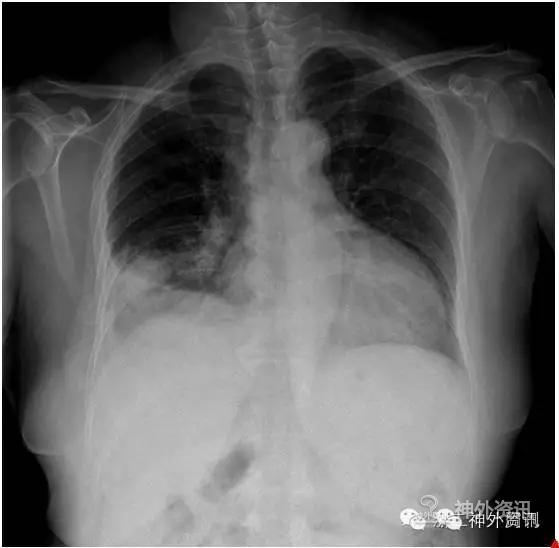

患者入院后行常规化验及检查。垂体相关激素检查,除泌乳素782.3mIU/L,高于正常一倍多以外,皮质醇、ACTH、TSH、生长激素、黄体生成素、卵泡刺激素、孕酮、雌二醇、睾酮等均正常。视力视野检查提示左眼失明,右眼颞侧偏盲。术前常规胸片(图2)提示右下肺部感染伴胸腔积液,建议抗炎后复查。向患者家属交待可选择肺部抗感染好转后再手术治疗,及因在抗感染过程中可能双眼视力会进一步下降,早期手术必要性等。家属商量后选择先行手术治疗。

图2. 胸片提示右下肺部感染伴胸腔积液,建议抗炎后复查。